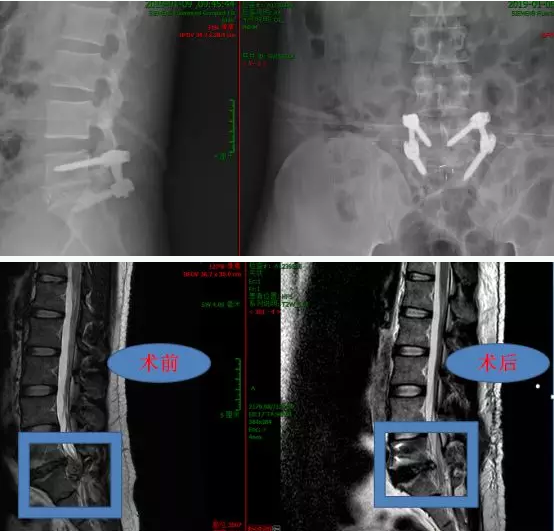

手术由何升华主任担任主刀医师

术中共取出游离髓核组织3大块

术后复查磁共振显示:脱出髓核被彻底拿干净,硬膜囊膨隆,硬膜外间隙清晰可见。